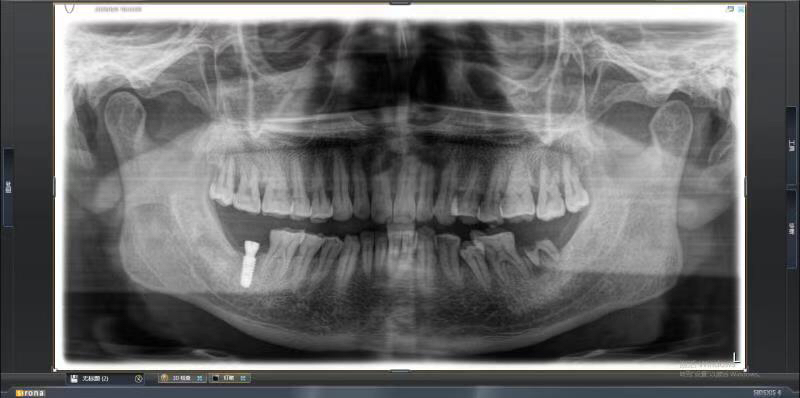

患者中年男性,右下7号牙龋坏未及时处理至残根无法修复,CT检查发现骨量尚可,可以即拔即种,并且不需要植骨,节省了患者治疗周期,整个治疗过程用了4个月患者就戴上了牙齿。